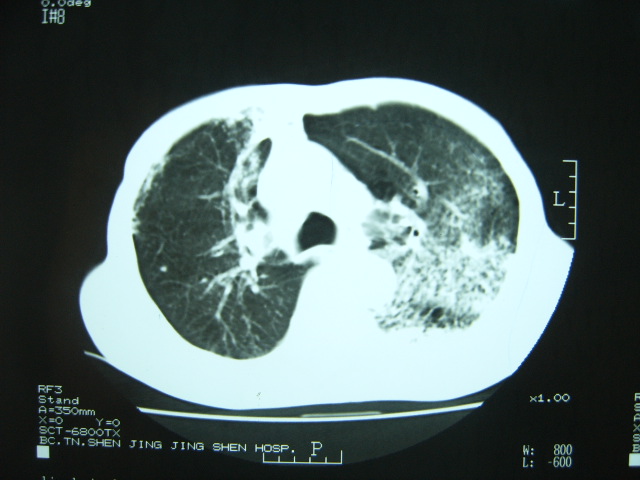

男74岁,咳嗽,寒战,低烧。有糖尿病史。

考虑:1、左下肺脓肿;不排除霉菌感染

2、双肺结核。

1、左下肺肺脓肿,合并霉菌球形成?.2、双肺陈旧性病灶.3、右上肺病灶警惕瘢痕癌,建议定期复查.

两肺结核,左下肺大片实变,内见空洞性病变,壁不规则,结合糖尿病史,考虑:结核性?霉菌性?建议结合实验室检查或治疗后复查。